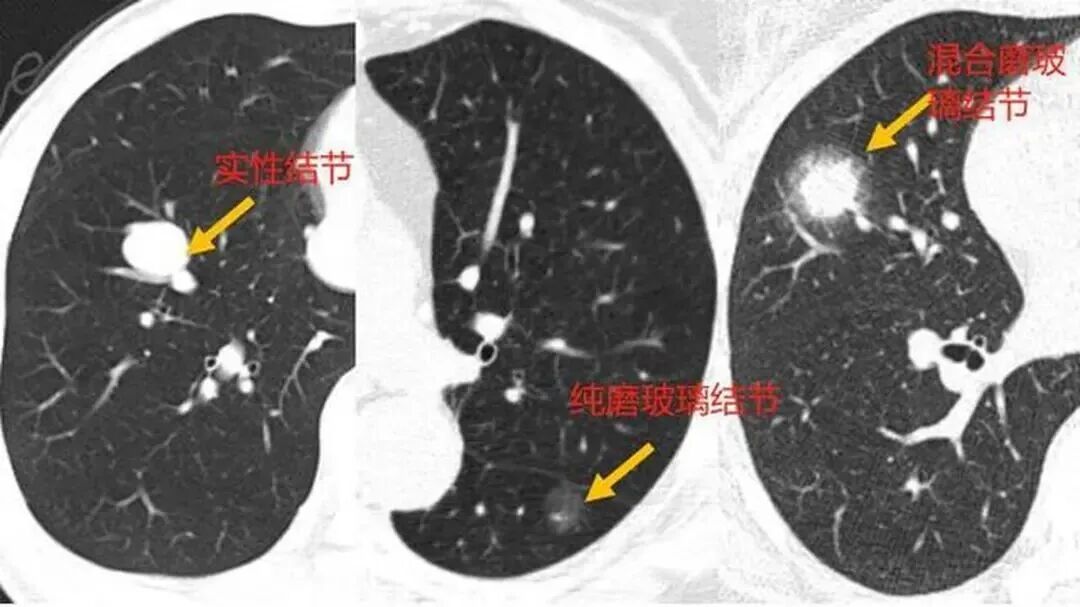

点击蓝字 关注我们 前 言 “体检报告一出,甲状腺结节、乳腺结节、肺结节……仿佛一夜之间,人人都带上了‘结节标签’。”这是很多人在体检后共同的焦虑。央视新闻在9月初的一期报道中,就点出了这一社会热点:结节高发,尤其在年轻人群体中愈发常见,朋友圈里甚至流传着“十人九结节”的说法。结节会不会变成癌?要不要立刻手术?为什么现代人越来越容易被检出结节? 与此同时,医学前沿传来好消息:天津医科大学团队在《Thoracic Cancer》期刊上发表了一例广泛期小细胞肺癌患者案例。患者在接受PD-L1增强型异体NK细胞回输联合治疗后,仅三个月,肺部多发结节明显缩小甚至消退。结节的流行与免疫疗法的突破,似乎在同一个时间点碰撞,为公众解答“如何面对结节”提供了新的视角。 01 结节爆发:为什么越来越常见 从体检中心的数据来看,甲状腺结节检出率已超过30%,乳腺结节在女性群体中占20%-30%,而肺结节在低剂量螺旋CT筛查中更是“常客”。到底是什么原因,让结节“无处不在”? 首先,是影像学手段的进步。十年前,大部分人没有接受过高分辨率...